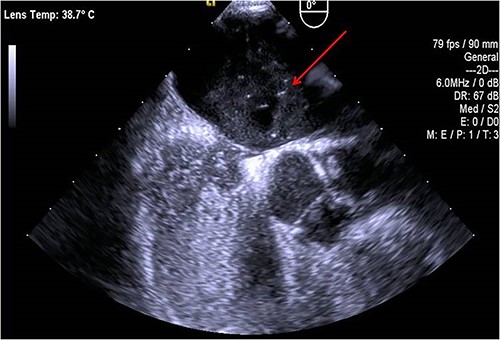

A 45-year-old female patient with a personal history of hypothyroidism, obesity, inferior parathyroidectomy for parathyroid adenoma and adnexectomy for benign ovarian cystadenoma presented with sudden onset dyspnoea as well as with pain, poikilothermia, pallor and weakness of left upper limb and hand. Physical examination showed peripheral O2 saturation of 80% and absence of radial and left brachial pulses. On Duplex ultrasound, deep or superficial vein thrombosis was not identified. On thoracic computed tomography angiography, bilateral pulmonary embolism (PE) and occlusion of the axillary artery were identified while aortic dissection was excluded (Fig.1). Given the concomitant upper limb ischemia and PE, the patient was hypocoagulated with low-molecular-weight heparin and underwent urgent thromboembolectomy and angiography, through a distal brachial surgical approach. Postoperatively, the patient recovered a radial and ulnar pulses. The embolic source was further investigated by transthoracic and transesophageal echocardiography, which identified a PFO (Fig.2). The patient was discharged on rivaroxaban for anticoagulation (20 mg once daily). During follow-up, thrombophilia screening was performed, including antiphospholipid antibody syndrome, factor V Leiden mutation, prothrombin gene mutation, antithrombin III defect, protein C and S deficiency assessments, but all results were negative. Considering the single event of right atrioventricular overload and flow-inversion through PFO associated with PE, PFO closure was not indicated.